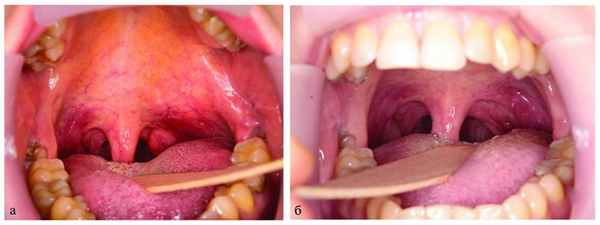

При поступлении: состояние больной удовлетворительное. Данные эндоскопии: просвет носоглотки деформирован на 1/2 за счет компрессии извне по левой стенке. В полости рта: просвет глотки сужен вдающимся слева, подслизисто расположенным опухолевым образованием, занимающим боковую поверхность ротоглотки слева в проекции дужки и за ней (рис. 2, см. на цв. вклейке) Рис. 2. Вид мягкого неба с выбуханием опухоли глоточного отростка в просвет ротоглотки (а); просвет ротоглотки после операции (б). . Контуры лица и шеи деформированы из-за объемного опухолевого образования левой околоушной СЖ. Образование плотноэластической консистенции, безболезненное при пальпации. Регионарные лимфатические узлы не увеличены и не пальпируются.

Метод хирургического лечения